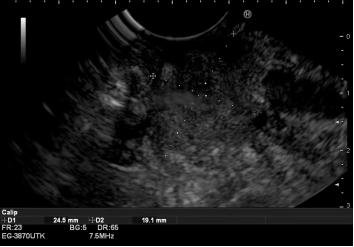

技术实施:毫米级精准操作,一站完成诊断与治疗

在充分的术前准备和家属沟通后,手术如期进行。精准诊断阶段:消化内科温蕾医生首先进行EUS检查。内镜前端的高频超声探头紧贴消化道壁,对胰头部病灶进行了360度无死角扫描,清晰地显示了肿瘤的大小、边界及其与周围血管的毗邻关系。在实时超声的精确引导下,穿刺针犹如“GPS导航”般,毫厘不差地穿越十二指肠壁,直达肿瘤核心,成功获取了足量的条索状组织,为病理诊断奠定了坚实基础。紧急治疗阶段:随后,无缝切换至ERCP操作。蒋承志医生熟练地把十二指肠镜抵达十二指肠乳头,造影清晰显示肝外胆管重度狭窄。导丝顺利通过狭窄段,一枚覆膜金属支架被精准释放于梗阻部位。瞬间,淤积的胆汁得以顺畅流入肠道,梗阻成功解除。整个手术过程流畅,患者无特殊不适。术后病理结合免疫组化,迅速明确诊断为胰腺导管腺癌。随着支架起效,患者黄疸快速消退,肝功能指标显著改善,为后续可能进行的抗肿瘤治疗赢得了宝贵时间和身体条件。